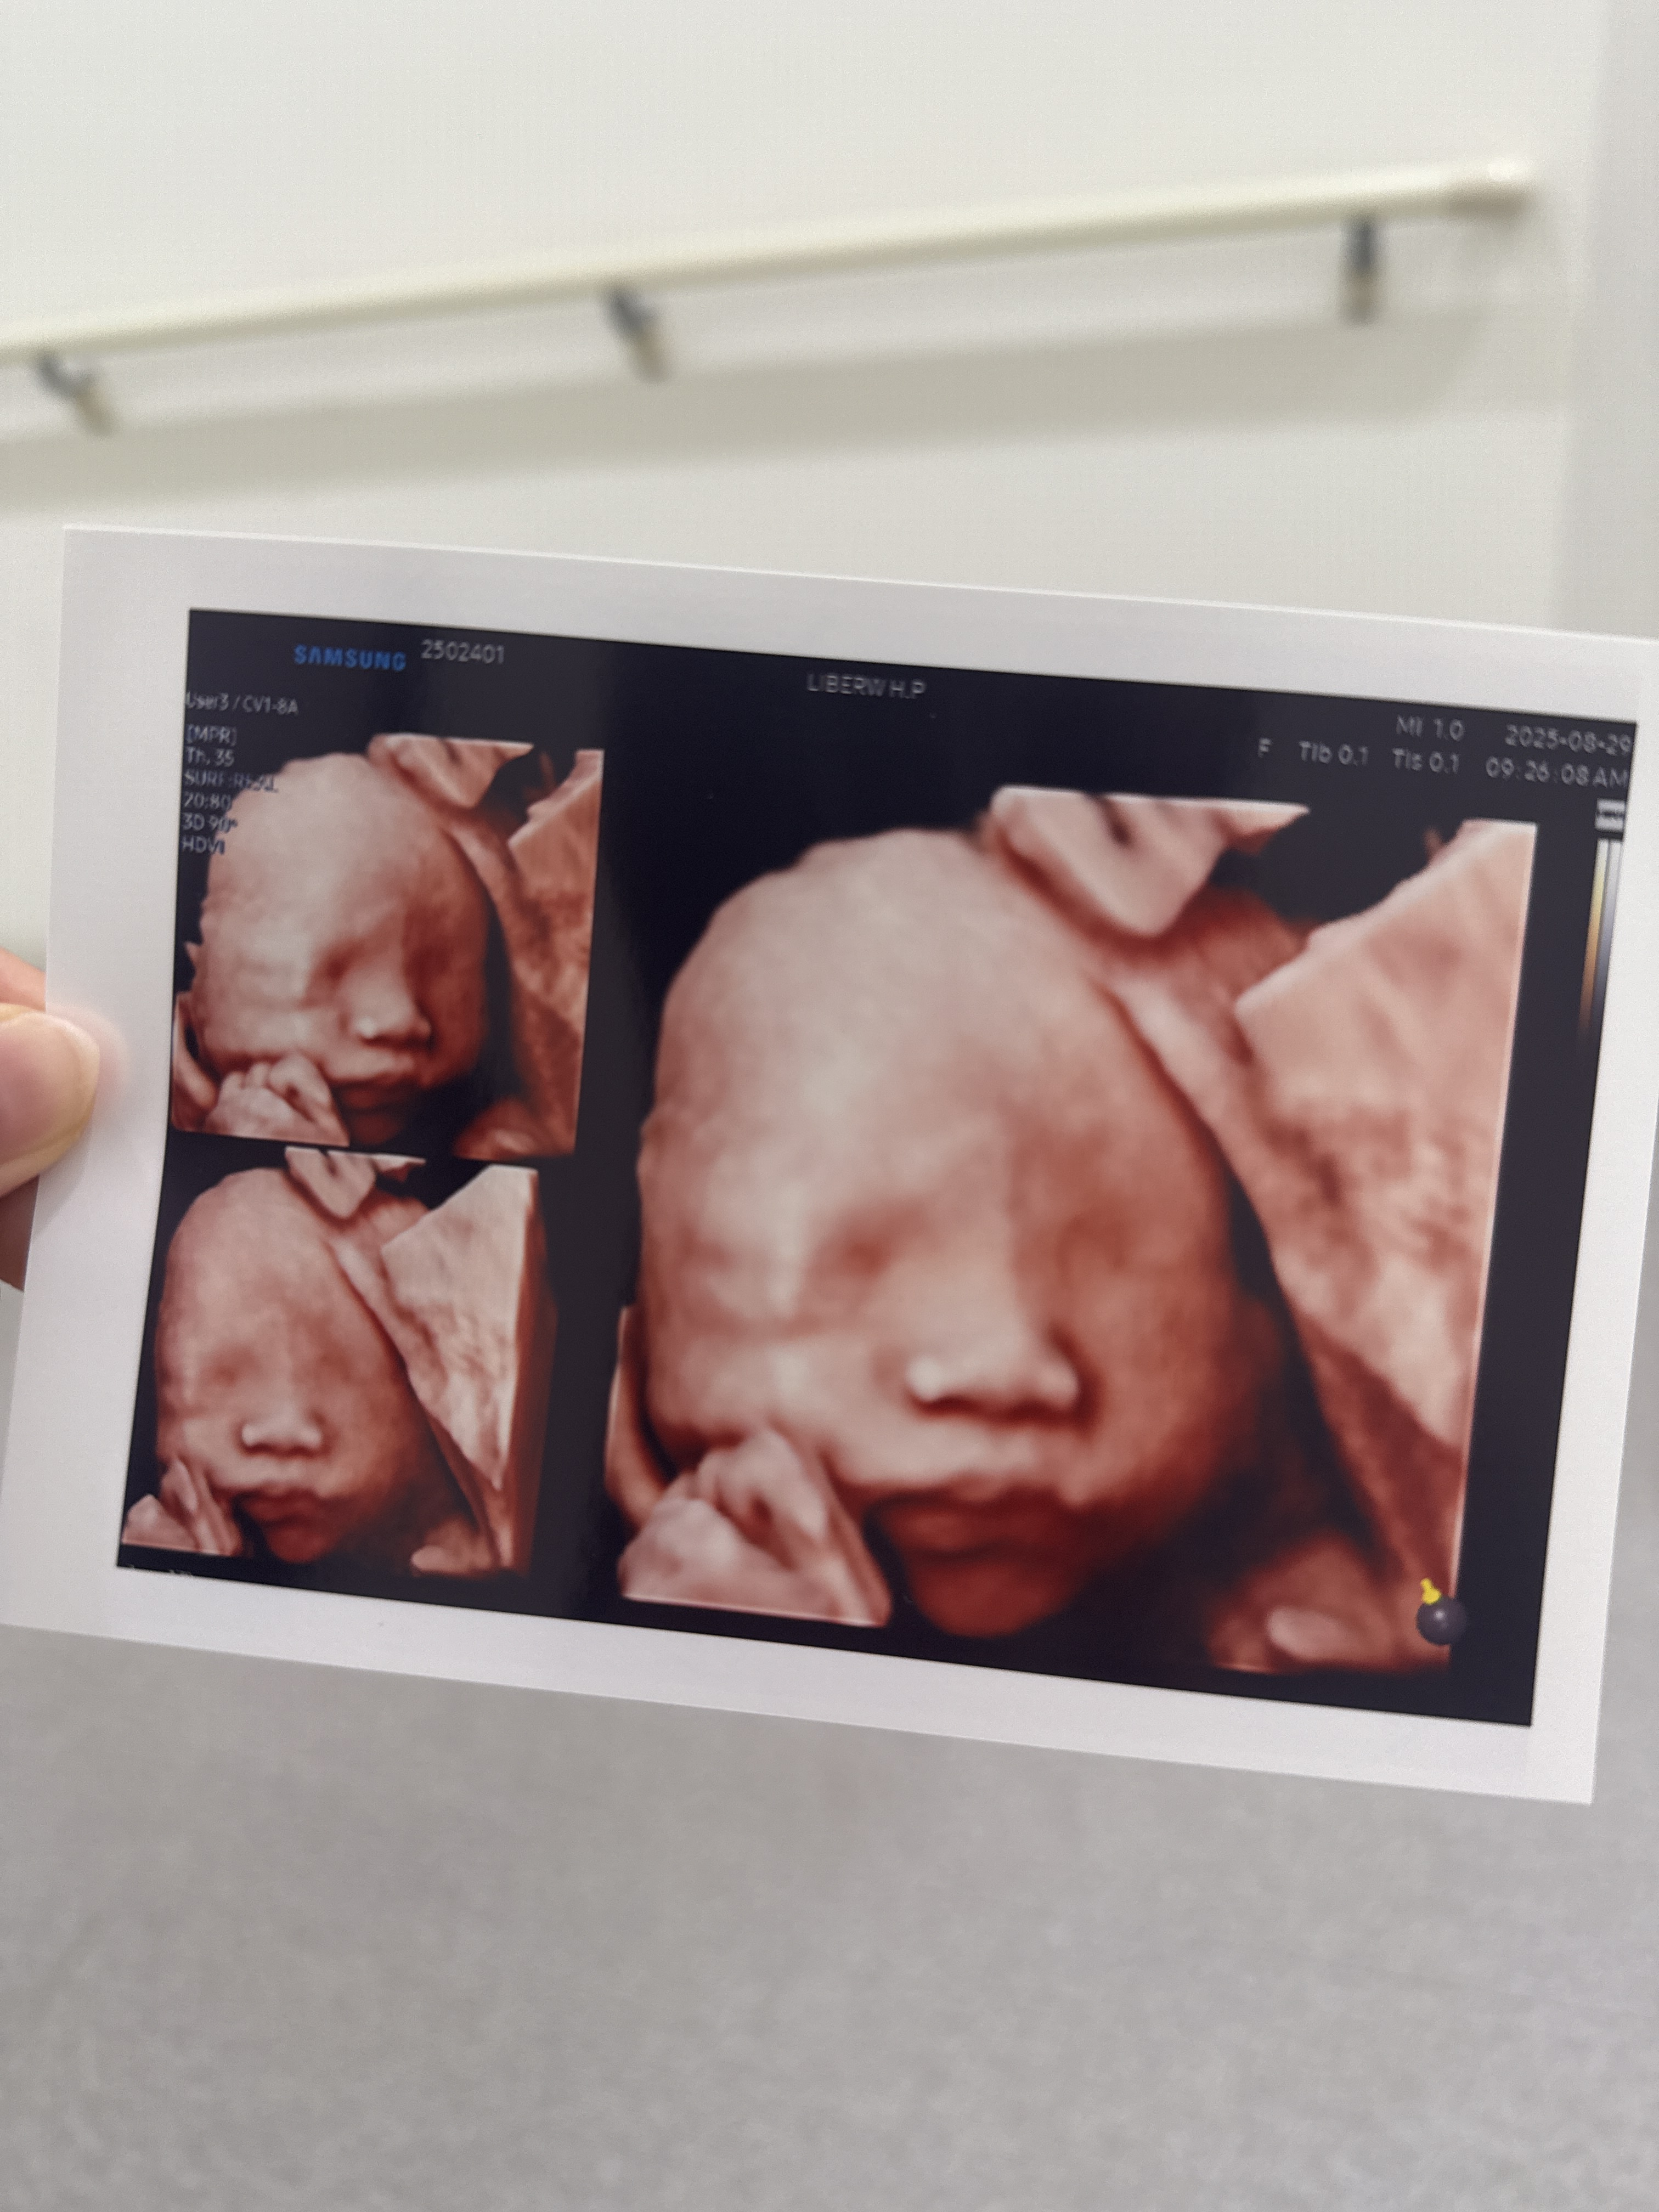

드디어 성공한 입체초음파

3차까지 실패하면 못본다해서 걱정했는데

성공했다 얏호👏👏

진짜 조~금 기대했는데,

사진 받으니까 너무 귀여워서 혼났다ㅠㅠ

손으로 턱 괴고 있었는데,

왤케 귀여운거니 사탕아...

내 최애사진은 입 벌린 사탕이ㅋㅋㅋㅋ

양수 마시는건지 입벌리고 있던게

딱 포착됬다 !!!

귀여워 죽겠네🤍🤍🤍

같이 찍어주신 사탕이 손이랑 발

길쭉길쭉한게 이뻤다..^^